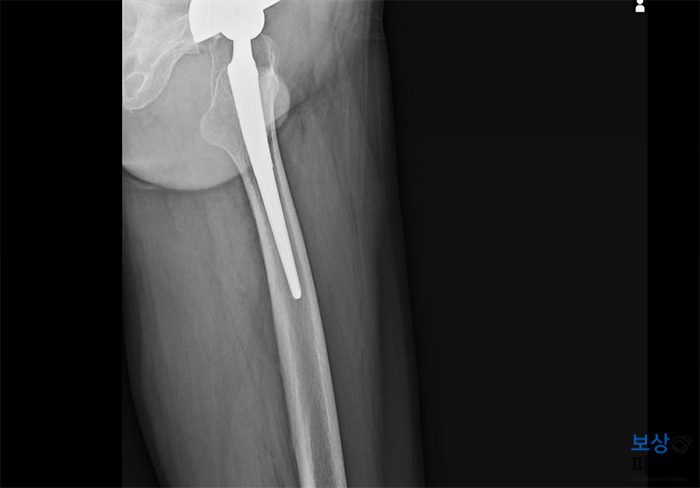

K 님은 뜻밖에도 양측 대퇴골두 무혈성괴사 진단이 나오게 되었는데요. 나이가 적은 편이 아니셔서 재생술이나 구제술은 어려웠고, 결국 양쪽 고관절 모두 인공관절 치환술을 시행하게 되었습니다.

수술은 성공적으로 끝났지만 이후 정상적으로 보행하시기 전까지는 수개월간 물리치료와 재활치료가 필요하셨습니다.